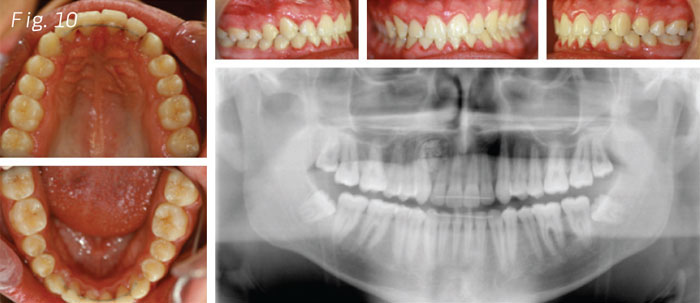

We had to make good lateral and protrusive adjustments so we could have stability and suggested to the patient just to use an Essix Ace .040 as an upper retainer and fixed retainers from lateral to lateral on upper and from cuspid to cuspid on the bottom (Fig. 10).